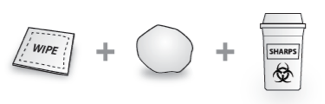

Nicht in der Packung enthalten: